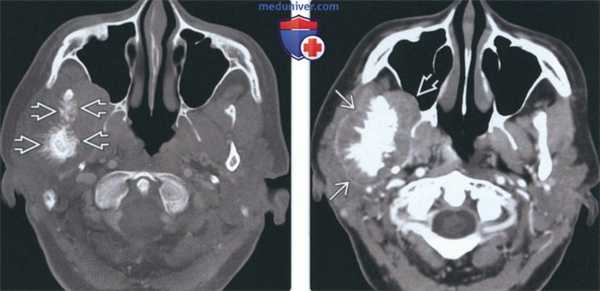

(Слева) На аксиальной КТ в костном окне на уровне сигмовидной вырезки справа визуализируется остеосаркома ветви и мыщелка нижней челюсти. Кортикальные пластинки утолщены, определяется лучистая периостальная реакция вокруг пораженных участков кости. Обратите внимание на асимметричный отек мягких тканей жевательного пространства и щеки справа.

(Справа) На аксиальной КТ с КУ у этого же пациента визуализируется опухоль, смещающая околоушную железу кзади и кнаружи, и вероятно, прорастающая в нее. Опухоль распространяется в правую верхнечелюстную пазуху.

3. КТ при остеосаркоме височно-нижнечелюстного сустава (ВНЧС):

• КТ с КУ:

о Умеренное контрастирование солидного компонента

• КЛКТ и КТ в костном окне:

о Опухоль часто разрушает кортикальную пластинку и прорастает в окружающие мягкие ткани, формируя объемное образование

о Мыщелок может выглядеть увеличенным с «пятнистой» картиной костной ткани